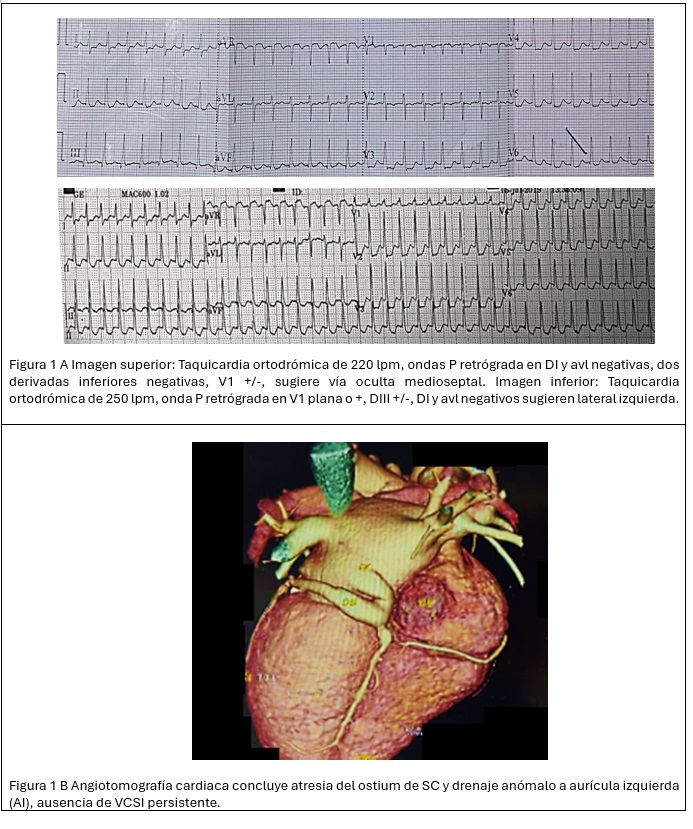

Introducción: Dentro de las taquicardias supraventriculares en la población pe...

Introducción: Dentro de las anomalías cardiacas congénitas se ha visto incide...